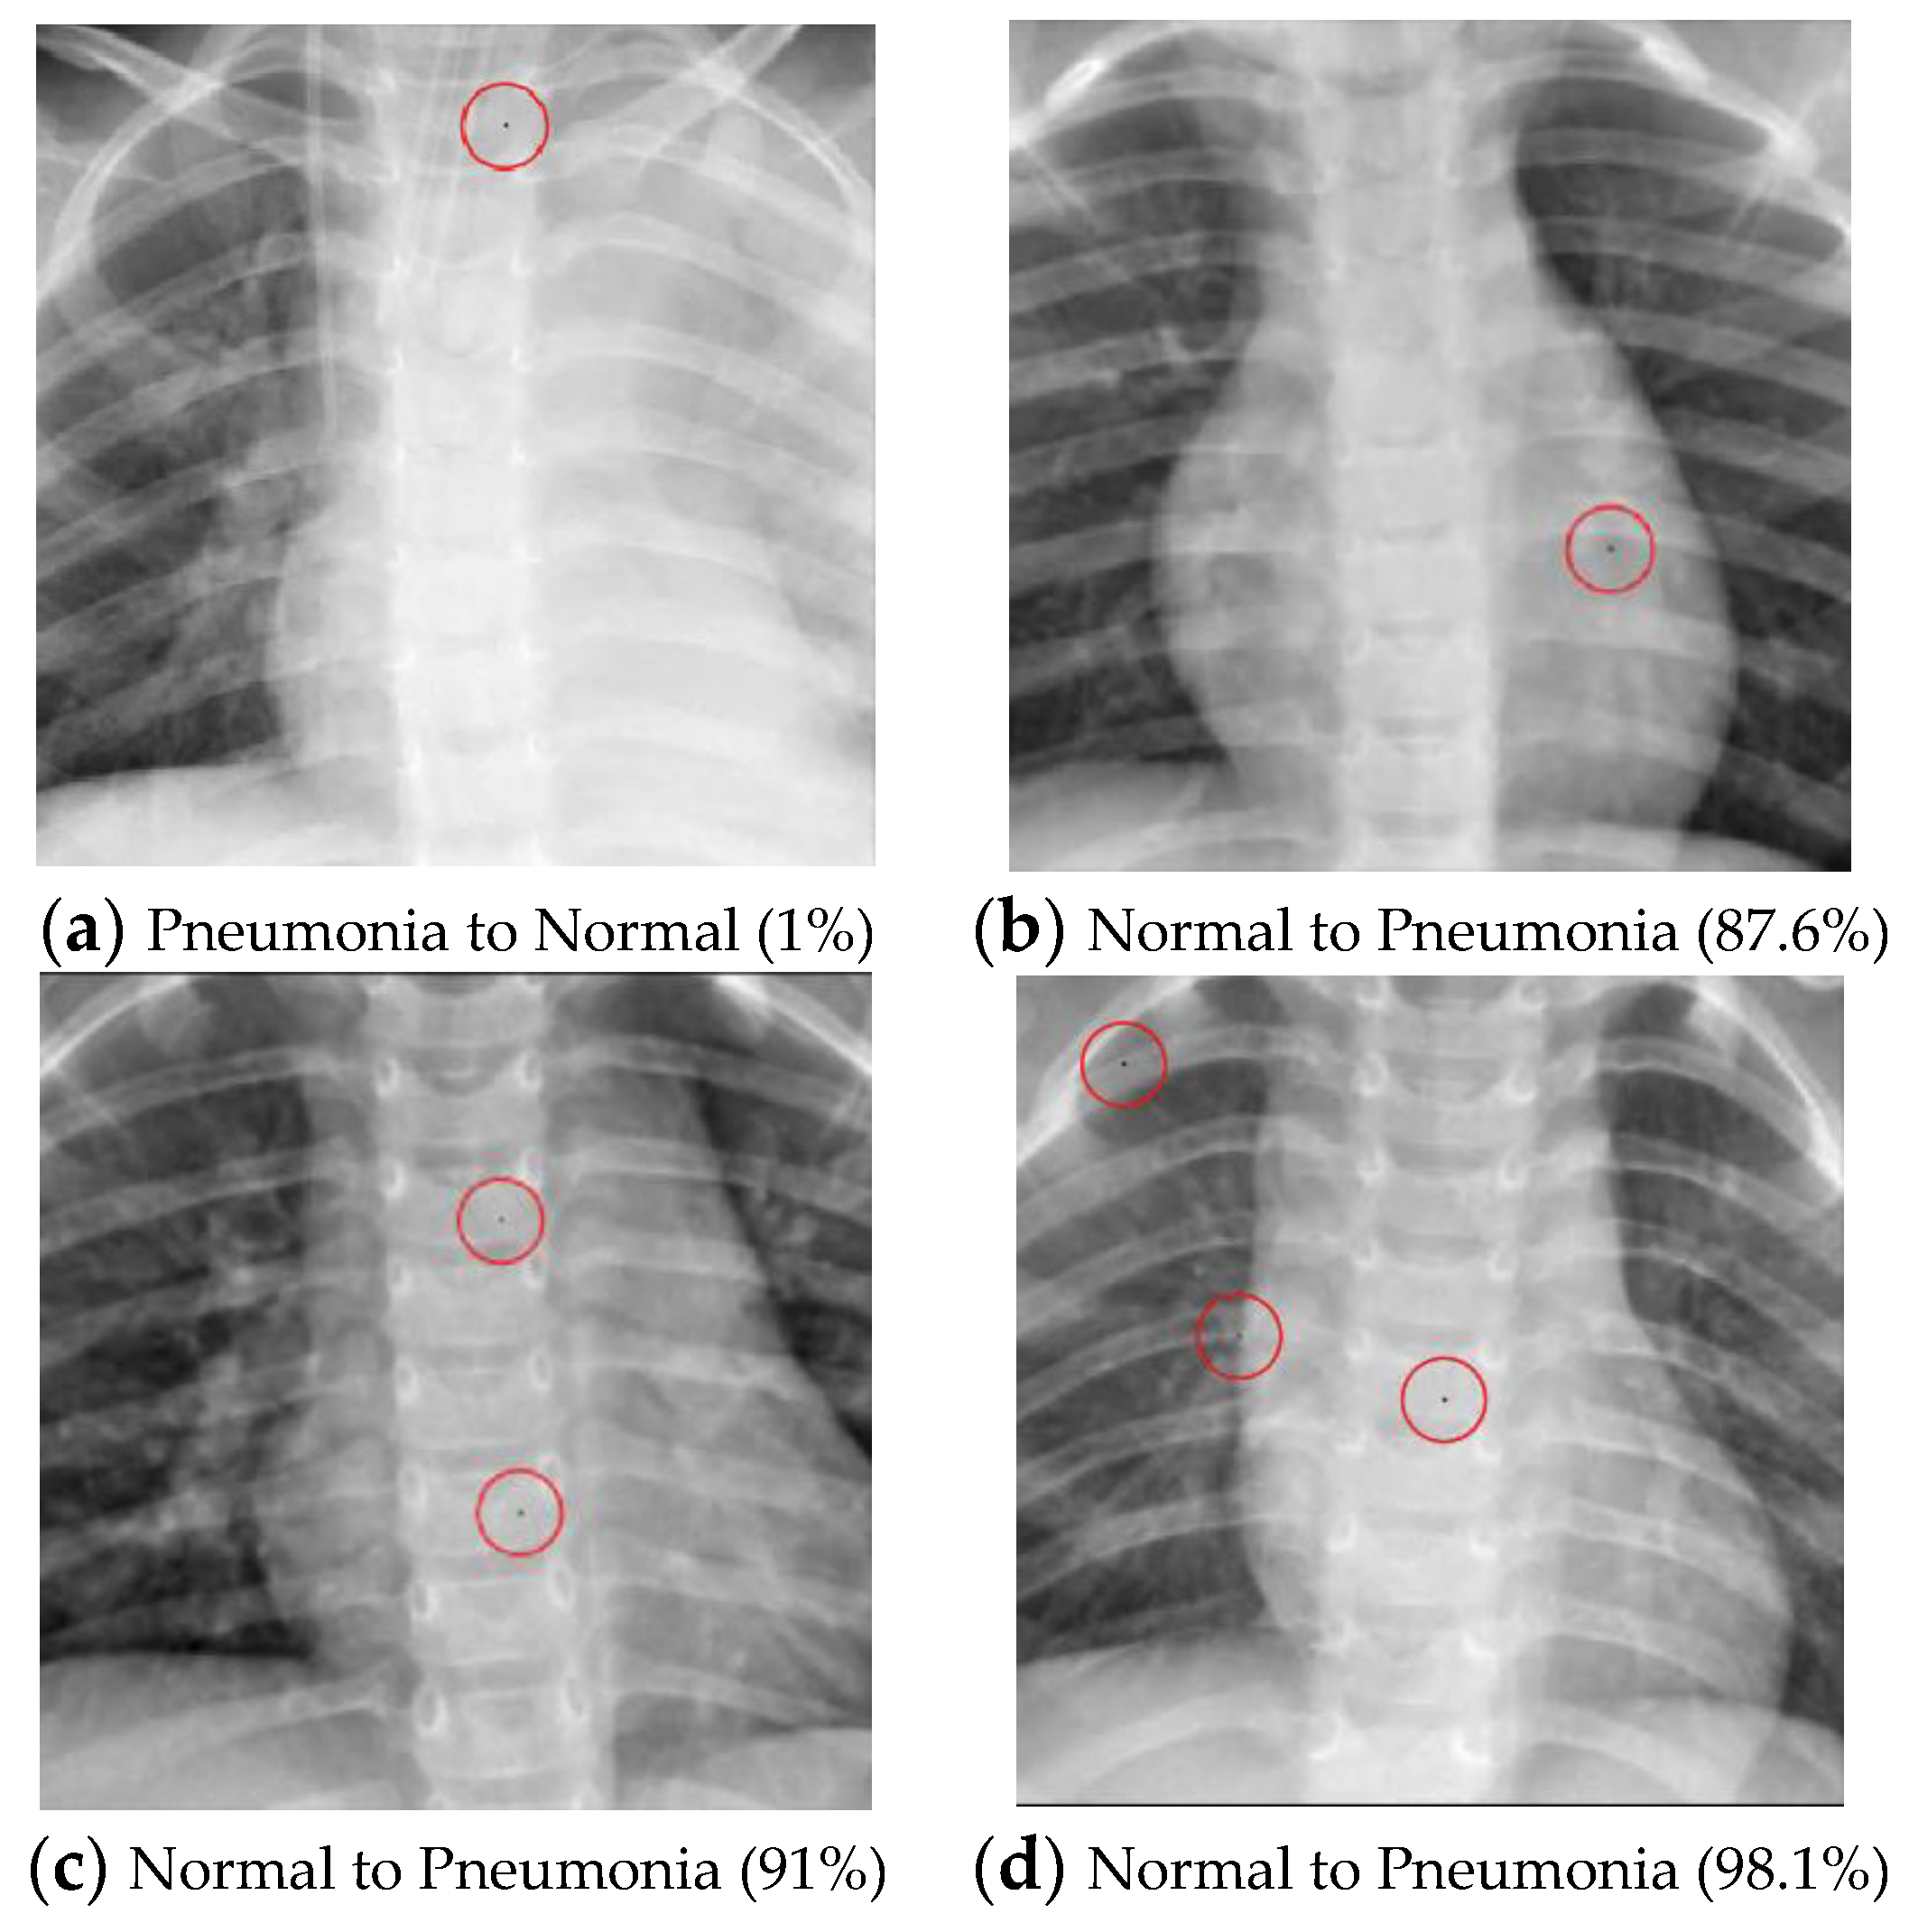

• Example of successfully attacked images

Because 100 experiments will be conducted on each class in each dataset, and there will be a large number of successful images if the success rate is high, only one successful image will be presented for each class. The successfully modified image will be shown with a red circle to indicate the modified pixel. There will be two description lines under each image: a bold black line to indicate the original class and a bold red line to show the class that has been transformed. The number in parentheses shows the confidence level of that class. Notably, there will be some confidence levels that indicate “~100%”. This represents a confidence level above 99.94% because the number will be rounded to one decimal point.

The Pneumonia dataset encompasses two different image classes, namely “Normal” and “Pneumonia”. A multi-pixel attack strategy was used on both classes in this research with the objective of transforming the images into their respective opposite categories.

As illustrated in Table 10, the success rate of converting normal images into pneumonia images is positively correlated with the number of perturbed pixels. However, the algorithm’s performance in transforming pneumonia images into normal images does not yield successful results, even with an increase in the perturbed pixels. The successful attack images are shown in Figure 4.

Figure 4. Examples of the attack results on the Pneumonia dataset with confidence level of ResNet50: (a) One-pixel attack turning Pneumonia to Normal; (b) One-pixel attack turning Normal to Pneumonia; (c) Two-pixel attack turning Normal to Pneumonia; (d) Three-pixel attack turning Normal to Pneumonia.